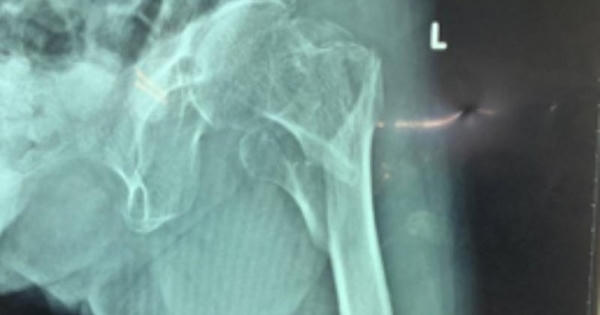

BV Chấn thương-Chỉnh hình TP HCM vừa nối lại thành công các mảnh xương gãy cho cụ bà 101 tuổi bị té ngã.